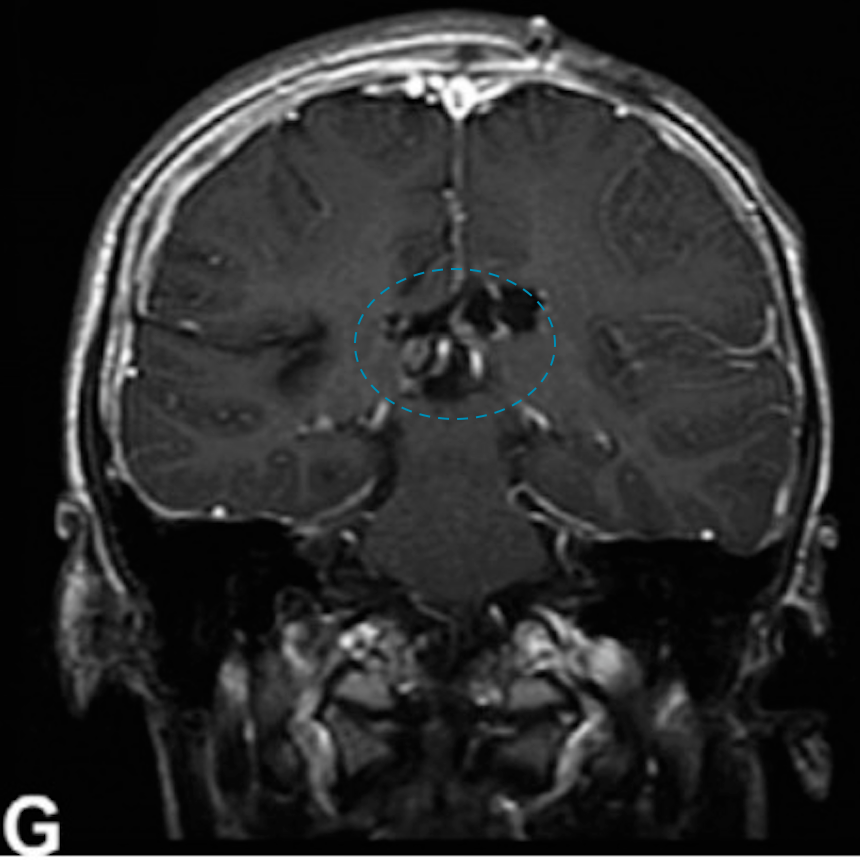

(G)随访图像显示6年后病情稳定。